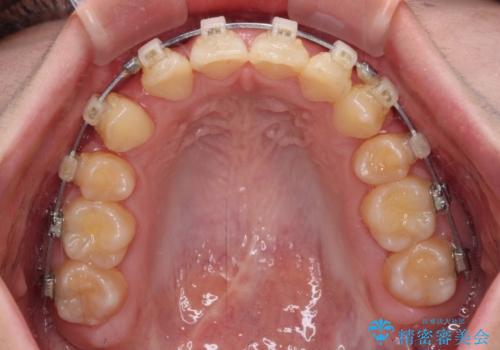

- 矯正装置

- クリアブラケット

下顎の左右側切歯2本が欠損しており、上顎歯列がデコボコとなっている状態でした。

下顎歯列に対して上顎歯列が相対的に大きくなっているため、デコボコとなっているだけでなく、下顎前歯が見えなくなるくらいのディープバイトにもなっていました。

上顎左右第一小臼歯2本を抜歯し、ワイヤー装置にて矯正治療を行うこととしました。